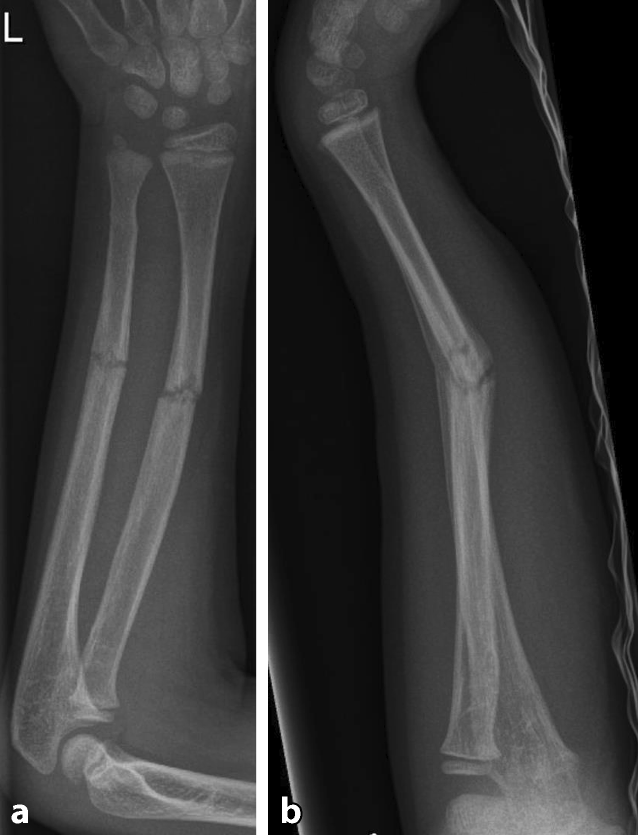

Abb. 1

Diaphysäre Grünholzfraktur des Unterarmschafts eines 6‑jährigen Jungen nach Skateboardsturz. ab Unfallröntgen in zwei Ebenen